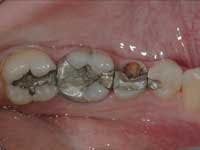

Less than one-half of the coronal tooth structure remaining (Figs. 1-6)

It is my opinion, regardless of the other factors present, that it is still advisable to place a post or posts in such teeth. Endodontically treated teeth with less than one-half of the coronal tooth structure remaining have a reduced chance of long-term service, and patients should be so advised as the treatment plan is developed.